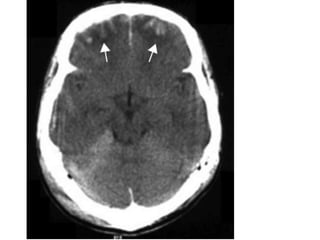

Multiple areas

of linear high

density are

seen within the

right cerebral

sulci

(arrows); these

represent

areas of acute

subarachnoid

haemorrhage

Subarachnoid Hemorrhage

Radiological features

● Non-contrast CT is sensitive within 4–5

hours of onset.

● Look for acute haemorrhage (increased

density) in the cortical sulci, basal

cisterns, Sylvian fissures, superior

cerebellar cisterns and in the ventricles.

● MRI is relatively insensitive within the

first 48 hours but is useful after this

time and in recurrent bleeds to pick up

subtle haemosiderin deposition